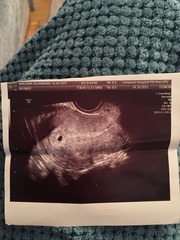

mrsunsure I had a scan and thought I was 6+5 but they said they only saw a sac and was more like 5 - here's the scan with just the sac, they said to come back in 10 days which were the longest 10 days of my life but I went back and they dated me as 6 weeks and saw a healthy heartbeat - here's the scan pic - fingers crossed for you, just remember that you only normally read the bad stuff on Google and all the forums but statistically you are more likely to have a healthy pregnancy than not - chin up xxx